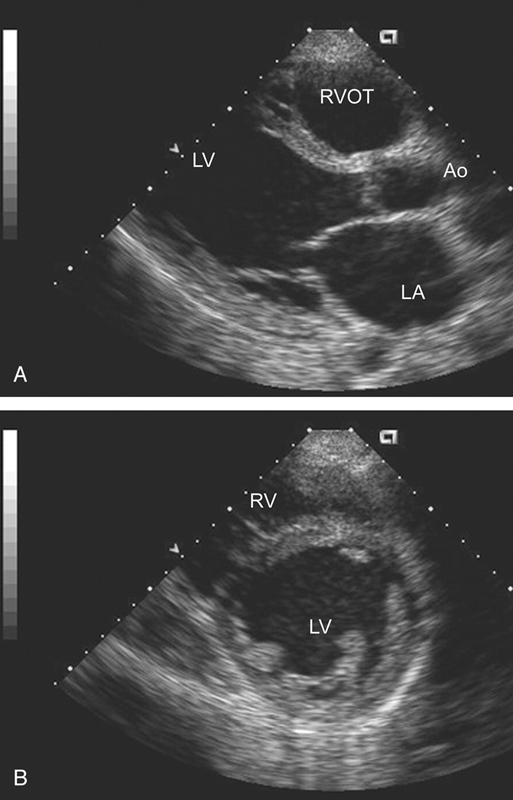

فحوصات تشخيصية لبعض امراض القلب والشرايين التاجية